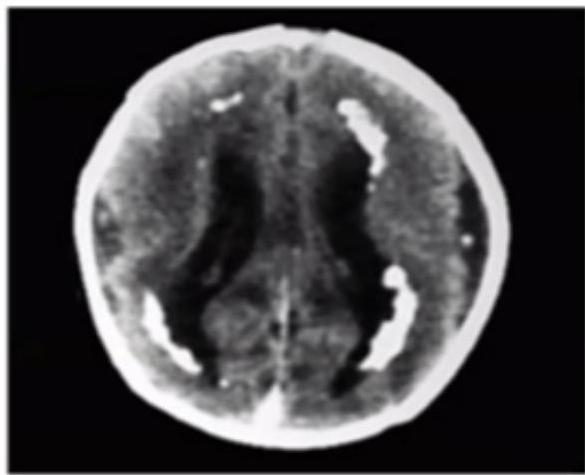

CMV Infection

Diagnosis? CMV.

CT finding? Periventricular calcification (vs Toxo which is scattered).

Findings:

- Microcephaly

- Jaundice

- Hearing loss

- Non-blanching rash

- Small for gestational age

- Calcification around the ventricles (C-shape)

Memory aid:

- C-shape calcification = CMV

Congenital Toxoplasmosis

This child was delivered with jaundice, HSM, wide spread rashes and progressive head enlarging. Mather gave history of contact with cats early in her pregnancy.

- Diagnosis?

- Congenital Toxoplasmosis “Lipic Vaginal” (Lipic Vaginal), - differential - CMV (paraventricular first image - c shaped)

CT Finding: Intracranial calcification (extensive cerebral calcifications) — scattered pattern.

- CNS calcifications (tram calcification pattern)

- Calcification in the border called “tram calcification”

- CMV has calcification around the ventricles (C-shape)